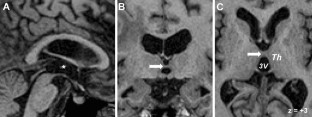

Fig. 1